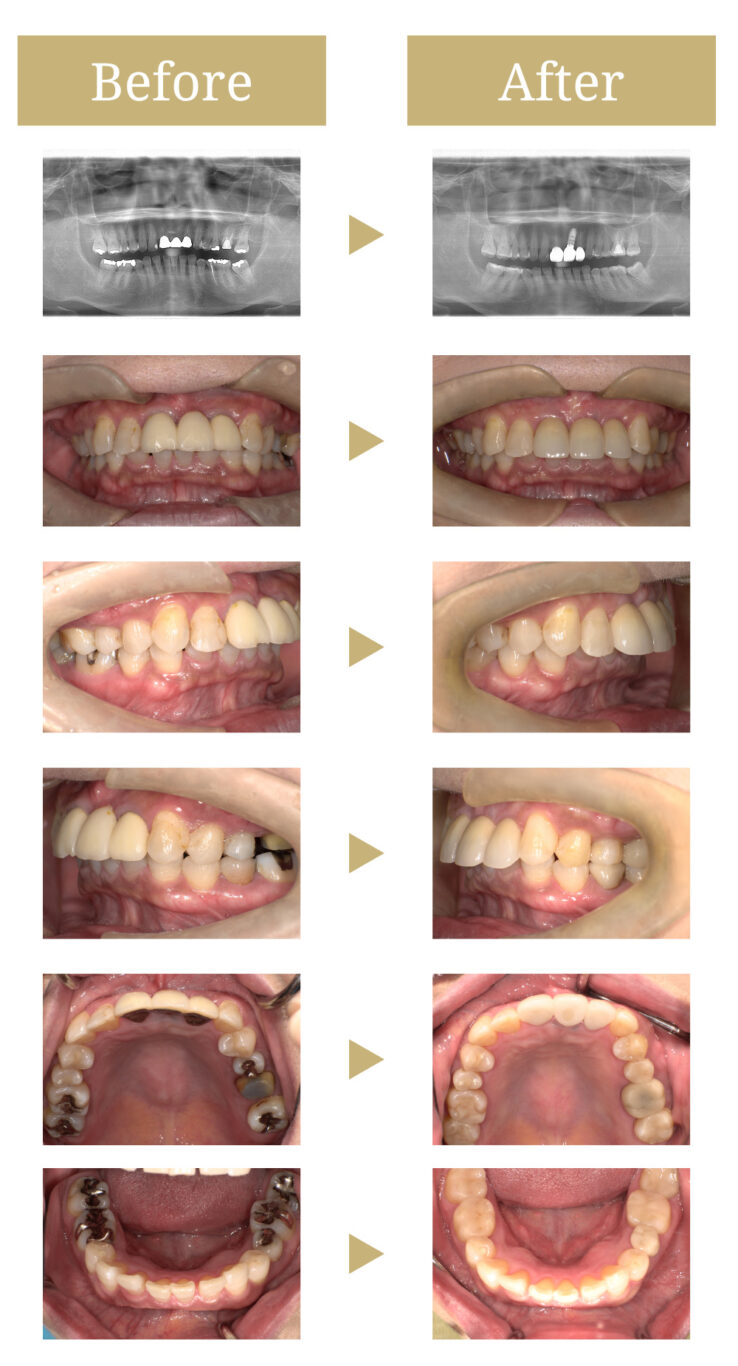

インプラントとセラミックの被せ物を用いて審美的、機能的に回復させた症例

奥歯は金属修復補綴物の劣化、隙間からの虫歯があったので治療内容を説明しました。

かみ合わせの負担から前歯のブリッジに負荷がかかり軽度の動揺があったので、インプラント治療を提案しました。

まず、はずれてしまった被せものは調整のうえ再セットしました。

臼歯部は劣化からの再治療を防げる点からセラミック補綴による治療を行いました。

前歯のブリッジを除去し、欠損部の左上前歯にインプラント補綴による治療を行いました。

金属修復補綴物の劣化、隙間からの虫歯がありました。

前歯のブリッジに負担がかかり軽度の動揺がありました。

セラミックにより補綴物の変形や劣化を抑えられ、虫歯の再治療のリスクを抑えられました。

前歯をブリッジからインプラント補綴にしたことによって、現存歯の咬合負担を減らし、清掃性もよくなりました。

動揺も軽減し、咬合関係も改善しています。